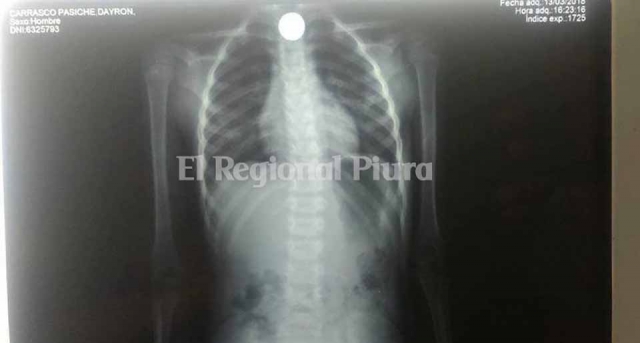

Los ancianos piden ayuda para extraerle el metal que se encuentra alojado en el esófago, pues urge que le realicen una endoscopia o, en caso contrario, una intervención quirúrgica.